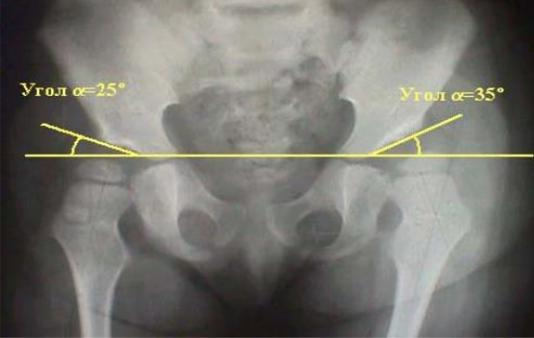

Ацетабулярный индекс - характеризует угол наклона крыши вертлужной впадины (Рис. 76). Он образован пересечением линии, соединяющей У-

образные хрящи с линией, проходящей от верхнего края крыши к центру У-

образного хряща. В здоровых суставах составляет до 20 град., при патологии -

больше 30 град.

Рис. 76. Ацетабулярный индекс.

У здорового новорожденного ацетабулярный угол равен в среднем 25-29

град (Рис. 77). В процессе роста уменьшается. К 1 году равен: мальчики-18,4

град., девочки-20 град. К 5 годам - меньше 15 град.

В норме у детей грудного возраста ацетабулярный угол доходит до 30

градусов, с возрастом он постепенно уменьшается и у детей в 14-15 лет его размеры составляют около 10 градусов.